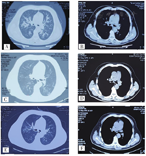

A、B:2020年10月8日,双肺渗出性病变(肺窗和纵隔窗);C、D:2020年10月21日,双肺渗出性病变明显吸收(肺窗和纵膈窗);E、F:2020年10月27日,双肺渗出性病变消失,局部纤维灶(肺窗及纵膈窗)

患者入院后给予吸氧、心电监护、血氧饱和度监测,糖皮质激素冲击治疗(氟美松40 mg加入液体中静脉滴注,1次/d,7 d后改为泼尼松30 mg口服,1次/d,14 d后减停),同时给予抗感染、保肝等综合治疗,抽吸患者足部水疱疱液并定期换药,给予妥布霉素地塞米松滴眼液滴眼。入院第3天,在吸氧6 L/min情况下患者血氧饱和度下降至85%,呼吸急促、困难,出现谵妄,血气分析:氧分压57 mmHg,二氧化碳分压57 mmHg,提示Ⅱ型呼吸衰竭,遂紧急予以气管插管、镇静状态下呼吸机辅助通气,并调整抗生素等治疗。入院第8天,患者病情好转,拔除气管插管后,患者意识清醒可自主呼吸,血氧饱和度维持98%,无憋喘症状,复查血常规及生化,白细胞及中性粒细胞比率仍然较高,其余指标均正常。结膜充血及皮肤大疱经治疗后恢复正常。继续予以营养支持、抗感染治疗后,患者病情明显好转。10月21日,入院第14天复查胸部CT显示双肺炎症大部分吸收,仅有少许渗出性病变(图2C、图2D),10月27日,入院第20天复查胸部CT显示少许纤维灶,余未见异常(图2E、图2F)。入院第25天行电子支气管镜检查:刷检物及灌洗液均未见病理细胞(图3A、图3B),患者入院第27天基本痊愈出院,嘱其1月后复查。患者于12月8日来我科复查,查体及辅助检查均正常,未述不适。